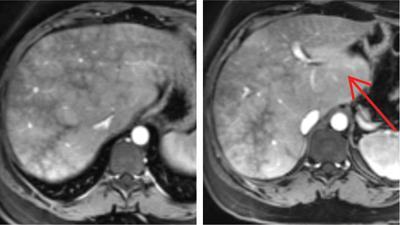

Shrinivas B. Desai, Ritu K. Kashikar, Shreya Shukla Radiological signs are classical and distinctive abnormalities characteristic of a disease. These can be seen on any imaging modality. Resemblance to commonly seen objects and patterns form the basis of radiological signs. The aim is to help the reader associate, understand and memorize these pathologies with the aid of signs. Various signs pertinent to hepatobiliary system are described in the chapter. Described on MRI when liver lesion shows a peripheral rim of high T2 signal intensity with the centre of the lesion appearing isointense to the background of noncirrhotic liver on T2WI mimicking an atoll. It is considered a characteristic sign of an inflammatory hepatic adenoma (image) but is only seen in about one-third of cases Extrinsic smooth impression over medial aspect of duodenum along its posteroinferior aspect, seen in pancreatic head pathologies like carcinoma. This sign is seen in pancreatic adenocarcinoma Presence of a persistently hyperattenuating dot within a lesion on arterial and portal venous CT. This corresponds with peripheral nodular enhancement seen on dynamic MR. Presence of bright dot suggests that the lesion is a hemangioma and helps in ruling out metastasis Ultrasound appearance of multiple cystic spaces or lesions that has been used to describe the appearance of an intraductal papillary mucinous neoplasm of the pancreas. Seen on contrast CT in portal hypertension. The appearance is based on resemblance to Medusa from Greek mythology. Dilated engorged paraumbilical veins radiating across umbilicus to join systemic veins is seen. This sign is seen in Caroli’s disease on contrast CT. Enhancing dots within dilated intrahepatic bile ducts represent portal radicles. Caroli’s disease Irregularly dilated pancreatic duct with multiple strictures and intervening dilatation with associated dilated side ductules resemble multiple lakes supplied by a single territory. Best seen in MRCP images. Chronic pancreatitis It is a finding on MRI and CT and is best seen on MRI T2-weighted and postcontrast T1-weighted sequences. Small necrotic/purulent areas in the pyogenic abscess ‘cluster’ together and then coalesce into a larger necrotic/purulent areas, eventually becoming a larger septated abscess cavity. At the periphery of these clusters: Associated with pyogenic hepatic abscesses and can help differentiate pyogenic abscesses from other types of liver lesions Abrupt termination of gas within the proximal colon at the level of radiological splenic flexure. The inflammatory exudates in pancreatitis extend to the phrenicocolic ligament giving rise to this sign Seen on grey scale ultrasound as a reverberation artifact when small calcific or highly reflective objects are imaged. The colour comet-tail artifact is an ultrasonographic sign seen in a number of situations when colour Doppler scanning is performed. This sign occurs in cases of traumatic right-sided diaphragmatic rupture with resultant partial herniation of liver through the defect. Separation of the herniated liver from its intra-abdominal component is via a small constriction at the level of diaphragm resembling a cottage loaf. Cottage loaf is a particular shape of bread in which larger and smaller roughly spherical balls are squashed together. Traumatic right-sided diaphragmatic rupture with resultant partial herniation of liver Bile eccentrically outlines luminal stone, creating a low attenuation crescent. Best seen on MRCP images. Choledocholithiasis Dilatation of both pancreatic duct and CBD is referred to as the double duct sign. Positive double duct sign suggests the diagnosis of carcinoma of the head of the pancreas and ampullary tumours and is hence considered ominous. Occasionally the sign may be seen in impacted gallstone in the distal duct. This feature is seen in patients with liver abscess on contrast-enhanced CT. A double, inner hyperattenuating and outer hypoattenuating rim is seen surrounding the hypodense abscess. The inner hyperattenuating rim corresponds to the enhancing abscess membrane, while the outer rim corresponds to the edema of the surrounding liver which appears hypodense and may show delayed enhancement. Liver abscess A positive duct penetrating sign is when a mass is penetrated by an unobstructed pancreatic duct; this makes focal pancreatitis the most likely cause rather than pancreatic carcinoma. This sign is best appreciated on MRCP (or ERCP). A radiographic sign that can be useful in differentiating between focal pancreatitis (inflammatory pancreatic mass) from pancreatic carcinoma. The duct-penetrating sign on MRCP is more helpful in differentiating between these two entities than a delayed enhancement pattern on CT or MRI It occurs when there is both limy bile and a gallstone in the common bile duct. The linear vertical radiopaque bile forms the line of the exclamation mark (i.e. !), whilst a more distal calculus forms the ‘dot’ at the end of the exclamation mark. Pathognomonic imaging sign of the rare diagnosis of limy bile on plain abdominal radiography Nonenhancing ruptured lesion with peripheral rim enhancement showing discontinuity from the rest of the liver and protruding from the liver surface is called the enucleation sign. Ruptured HCC Enlargement of the pericholecystic space. One of the signs of liver cirrhosis Can be seen on technetium 99m sulphur colloid scans of the liver and spleen, as well as CT studies. It occurs as a focal area of increased radiopharmaceutical uptake in the medial segment of the left hepatic lobe (segment IV) occurring as a result of SVC obstruction and portosystemic venous shunting between the superior vena cava and the left portal vein via the internal thoracic and paraumbilical veins. The equivalent of this sign may also be seen on contrast-enhanced CT scans as a hypervascular region. Budd–Chiari syndrome causes the hot spot sign in the caudate lobe

3) Bright dot sign